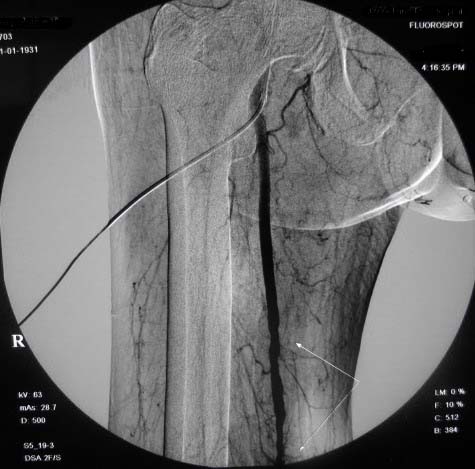

左下肢:

造影方法:取仰卧位,在局麻下,经右股动脉入路,采用改良seldingers技术,置入5f cobra导管于左髂外动脉行dsa,采集速度为2幅/秒,注射速率为6ml/秒,分节段造影;再将导管采用成襻技术放置于右侧髂外动脉,采用左侧同样的方法行dsa,术毕拔管、压迫止血约15分钟,包扎后嘱返病房,术后右足背动脉可扪及搏动。

右侧股浅动脉上、中段多处狭窄,下段闭塞。左侧股浅动脉多处狭窄,国动脉起始部狭窄。可以用球囊扩张配合动脉内溶栓或股浅动脉支架置入。多为糖尿病所致。

双侧股动脉及腘动脉多发狭窄,右股动脉下段闭塞并侧支形成。病变较广泛,球囊可试试,如病人经济不好,最好还是以药物治疗为主。个人意见。